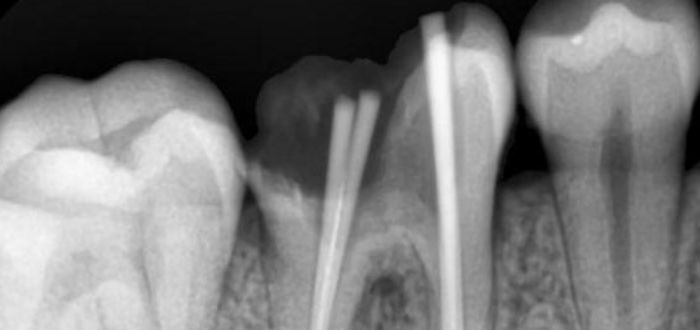

在了解根管治疗是否会疼痛之前,我们需要先了解一下根管治疗的原理。根管治疗的目的是清除牙齿内的感染物质,填充根管空腔,以防止感染再次发生。在进行根管治疗的过程中,牙医会使用镍钛文件从口腔良好进入到牙根的内部,然后将牙髓组织完全清除。这个过程可能会引起疼痛的感觉。